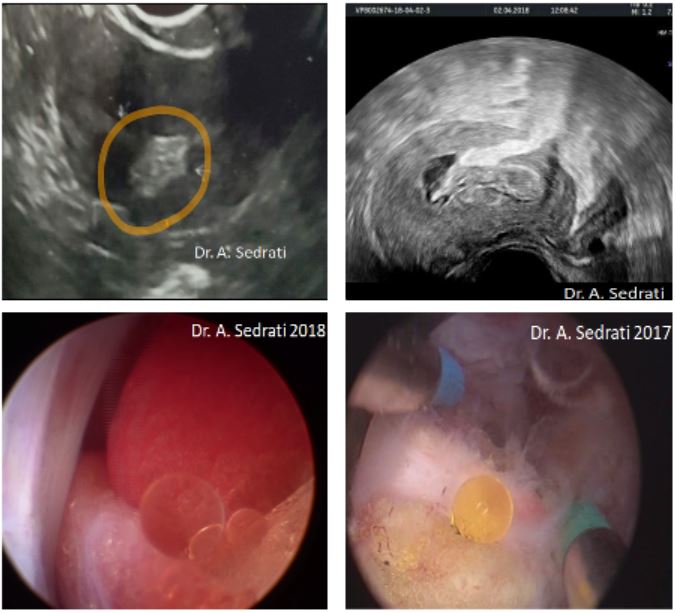

Omentum hysteroscopically appears as an intracavitary yellowish fat like lesion, initially raising the possibility of trophoblast or placental remnants. A case of intramyometrial fat metaplasia has also been reported in the literature, and is thus considered as a differential diagnosis. However, what seems to be pathognomonic of omentum, is that mechanical manipulation of the formation releases yellow drops of lipid nature. This could be termed the “fat drops sign”, or the “Sedrati sign” (fig.7;8), as Dr. Sedrati’s paper was the first in the literature to have described it.

These hysteroscopic findings should lead to increased vigilance and immediate termination of the procedure. Electrosurgery is prohibited. Laparoscopy is to be subsequently scheduled in order to liberate the incarcerated omentum and repair the uterine wall defect.